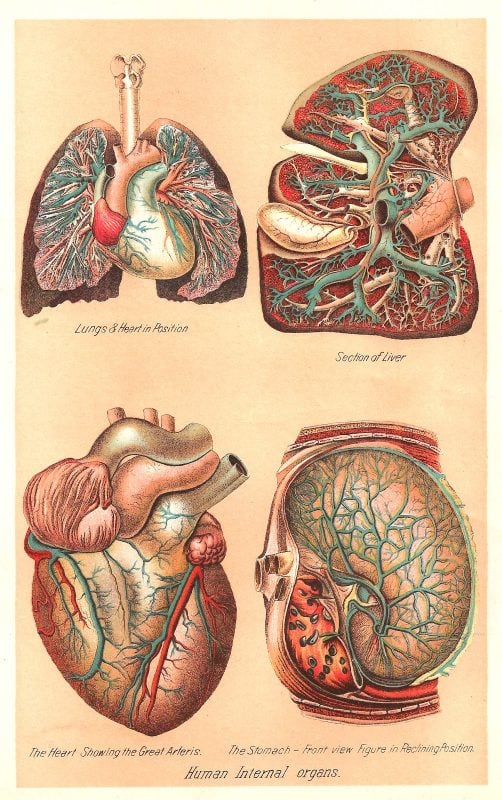

(2) Vintage Internal Organs via Antique Images